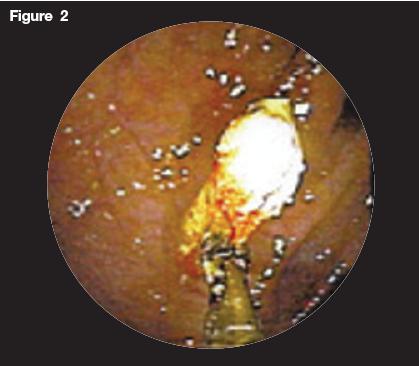

Laboratory analysis demonstrated a white blood cell count of 13 106/L(76% neutrophils). Findings from urinalysis were normal. Findings on a CT scan of the abdomen with contrast were normal with no evidence of appendicitis. Because of persistent abdominal pain with normal findings on the CT scan of the abdomen, colonoscopy was performed. Figures 1, 2, and 3 are images taken at the level of the terminal ileum. Figure 1 shows an impacted pill in the appendiceal orifice. Figure 2 shows the removal of the pill using forceps. Figure 3 shows mild residual inflammation of the appendiceal orifice after removal of the impacted pill.

Figure 2